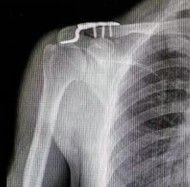

Большинство переломов могут быть диагностированы с помощью простых антеропостериальных рентгенограмм. Рентгенограммы наклона головки 20 ° устраняют влияние перекрывающихся грудных полостей. Пациенты должны быть рентгенограмма в положении самоподдерживания, чтобы лучше визуализировать смещение переломов. Веса для рентгенограммы помогает в оценке целостности ростральной клавикулярной связки в дистальной ключице или акромиоклавикулярной повреждениях суставов. Взятие рентгенограммы грудной клетки помогает исключить связанную торакальную травму, а укорочение может быть оценено путем сравнения с контралатеральной ключицей, а также исключая лопатологическую стенку.

3.5 Систематические сжатые пластины, реконструкционные пластины или пластиковые LCP могут использоваться для закрепления переломов ключицы. Пластины плавно расположены над или передней к ключице. Пластины более сильнее в биомеханических травмах, когда они расположены превосходно, особенно если внизу есть разбитый перелом, и их проще в визуализации. Необходима бикортикальная фиксация винтов, и отверстия должны быть просверлены с большой осторожностью, так как внизу риск повреждения нервов и кровеносных сосудов. Преимущества: безопасное бурение переднего винтового канала, приложение пластины, легкая контур.

Выбор имплантатов пластин зависит от размера бокового костяного блока. Для бокового костяного блока требуется минимум 3 бикортикальных винта. В идеале, винты натяжения должны использоваться для наклонных переломов. Если костный блок слишком мал для фиксации, может использоваться крючка ключица.